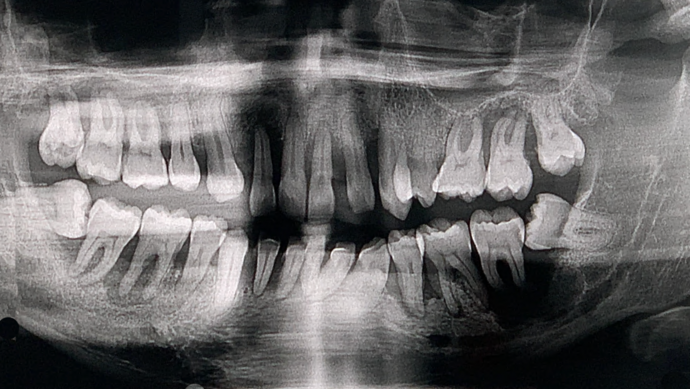

This busy business executive from NY suffered from chronic gum disease (periodontitis) due to genetics and unknown factors and had been to multiple dentists over the years and was tired of getting deep cleanings and still end up with several loose teeth in the mouth with massive bony destruction. As a young busy professional, he researched on getting the most scientific and durable treatment which could be done without several years in treatment and found Dr Bidra online. Dr. Bidra was able to successfully accomplish all his treatment goals by extracting all his teeth and installing Upper and Lower All on 4 implant bridges in 1 day. Most importantly, Dr Bidra did not need to perform any bone grafting procedures to accomplish this treatment.

Procedures : extractions, new implants, All on 4 , All on X, Teeth in a day, no bone grafting and full mouth reconstruction with monolithic zirconia bridges.